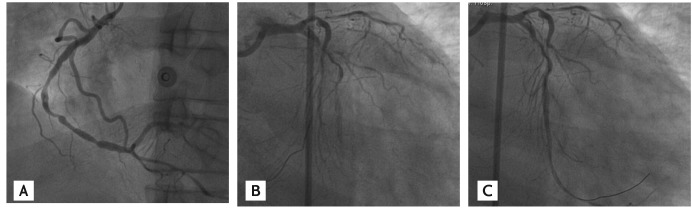

Figure 1

Diagnostic coronary angiography shows total occlusion of the proximal left circumflex artery as a culprit lesion, (A) a chronic total occlusion of the proximal left anterior descending artery (LAD) and (B) a complex 95% subtotal occlusion of the proximal right coronary artery with collateral circulation from the right ventricular branch to the LAD.